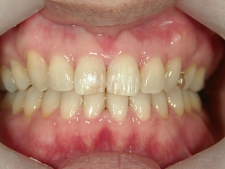

矯正歯科 治療前

矯正歯科(全顎ワイヤー矯正)治療後

全顎ワイヤー矯正 症例(2)

36歳女性 磐田市

在住

治療期間2年6

ヶ月